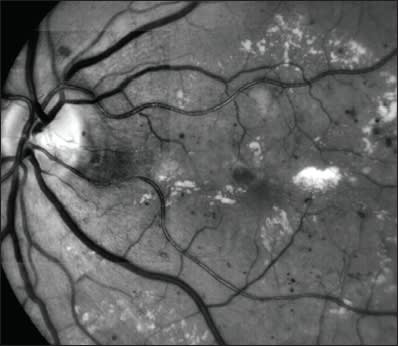

Figure 1. Clinicians must balance short-term and long-term outcomes when treating diabetic macular edema.